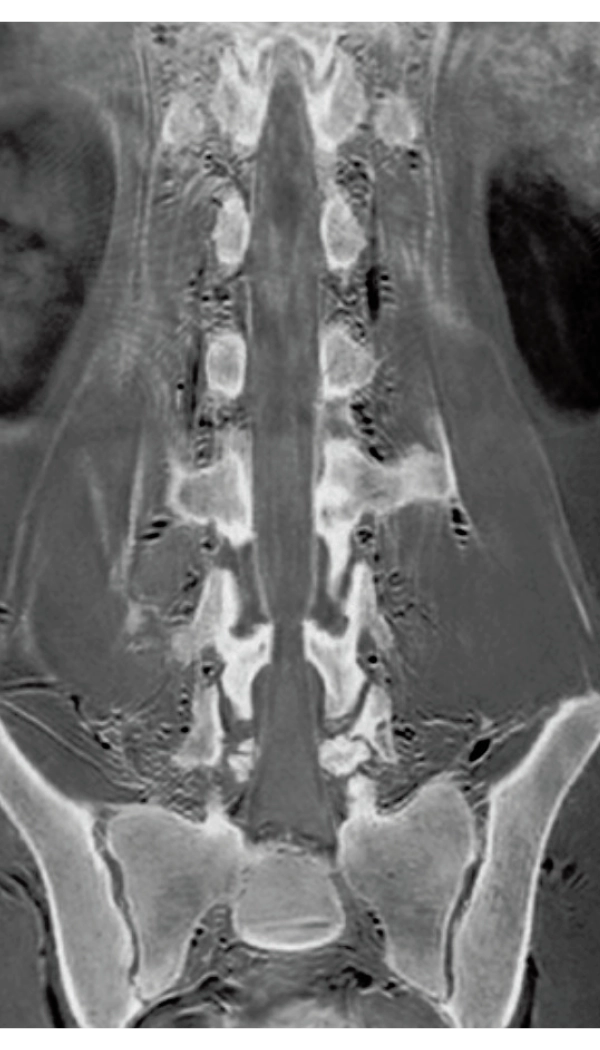

3D T1WI COR

2.2×1.5×1.5 mm

3st total scan time 0:54

3D MRCPA (MIP)

Lower extremity

non-contrast MRA (MIP)